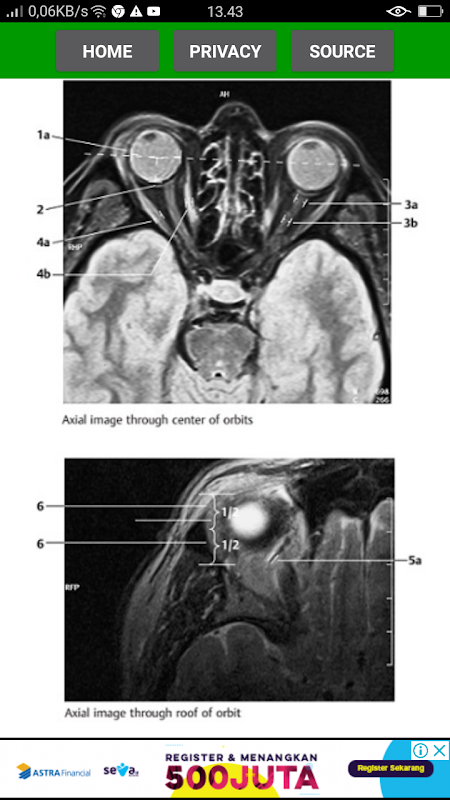

The key for any beginning radiologist who wishes to recognize pathological findings is to first acquire an ability to distinguish them from normal ones. This outstanding guide gives beginning radiologists the tools they need to systematically approach and recognize normal MR and CT images.

* Reference-quality images from the author's own teaching files show all standard normal findings as seen in CT and MRI

*Checklists in each section offer the reader a systematic way to approach the images

*Lists of standard measurements and tips for ruling out pathology